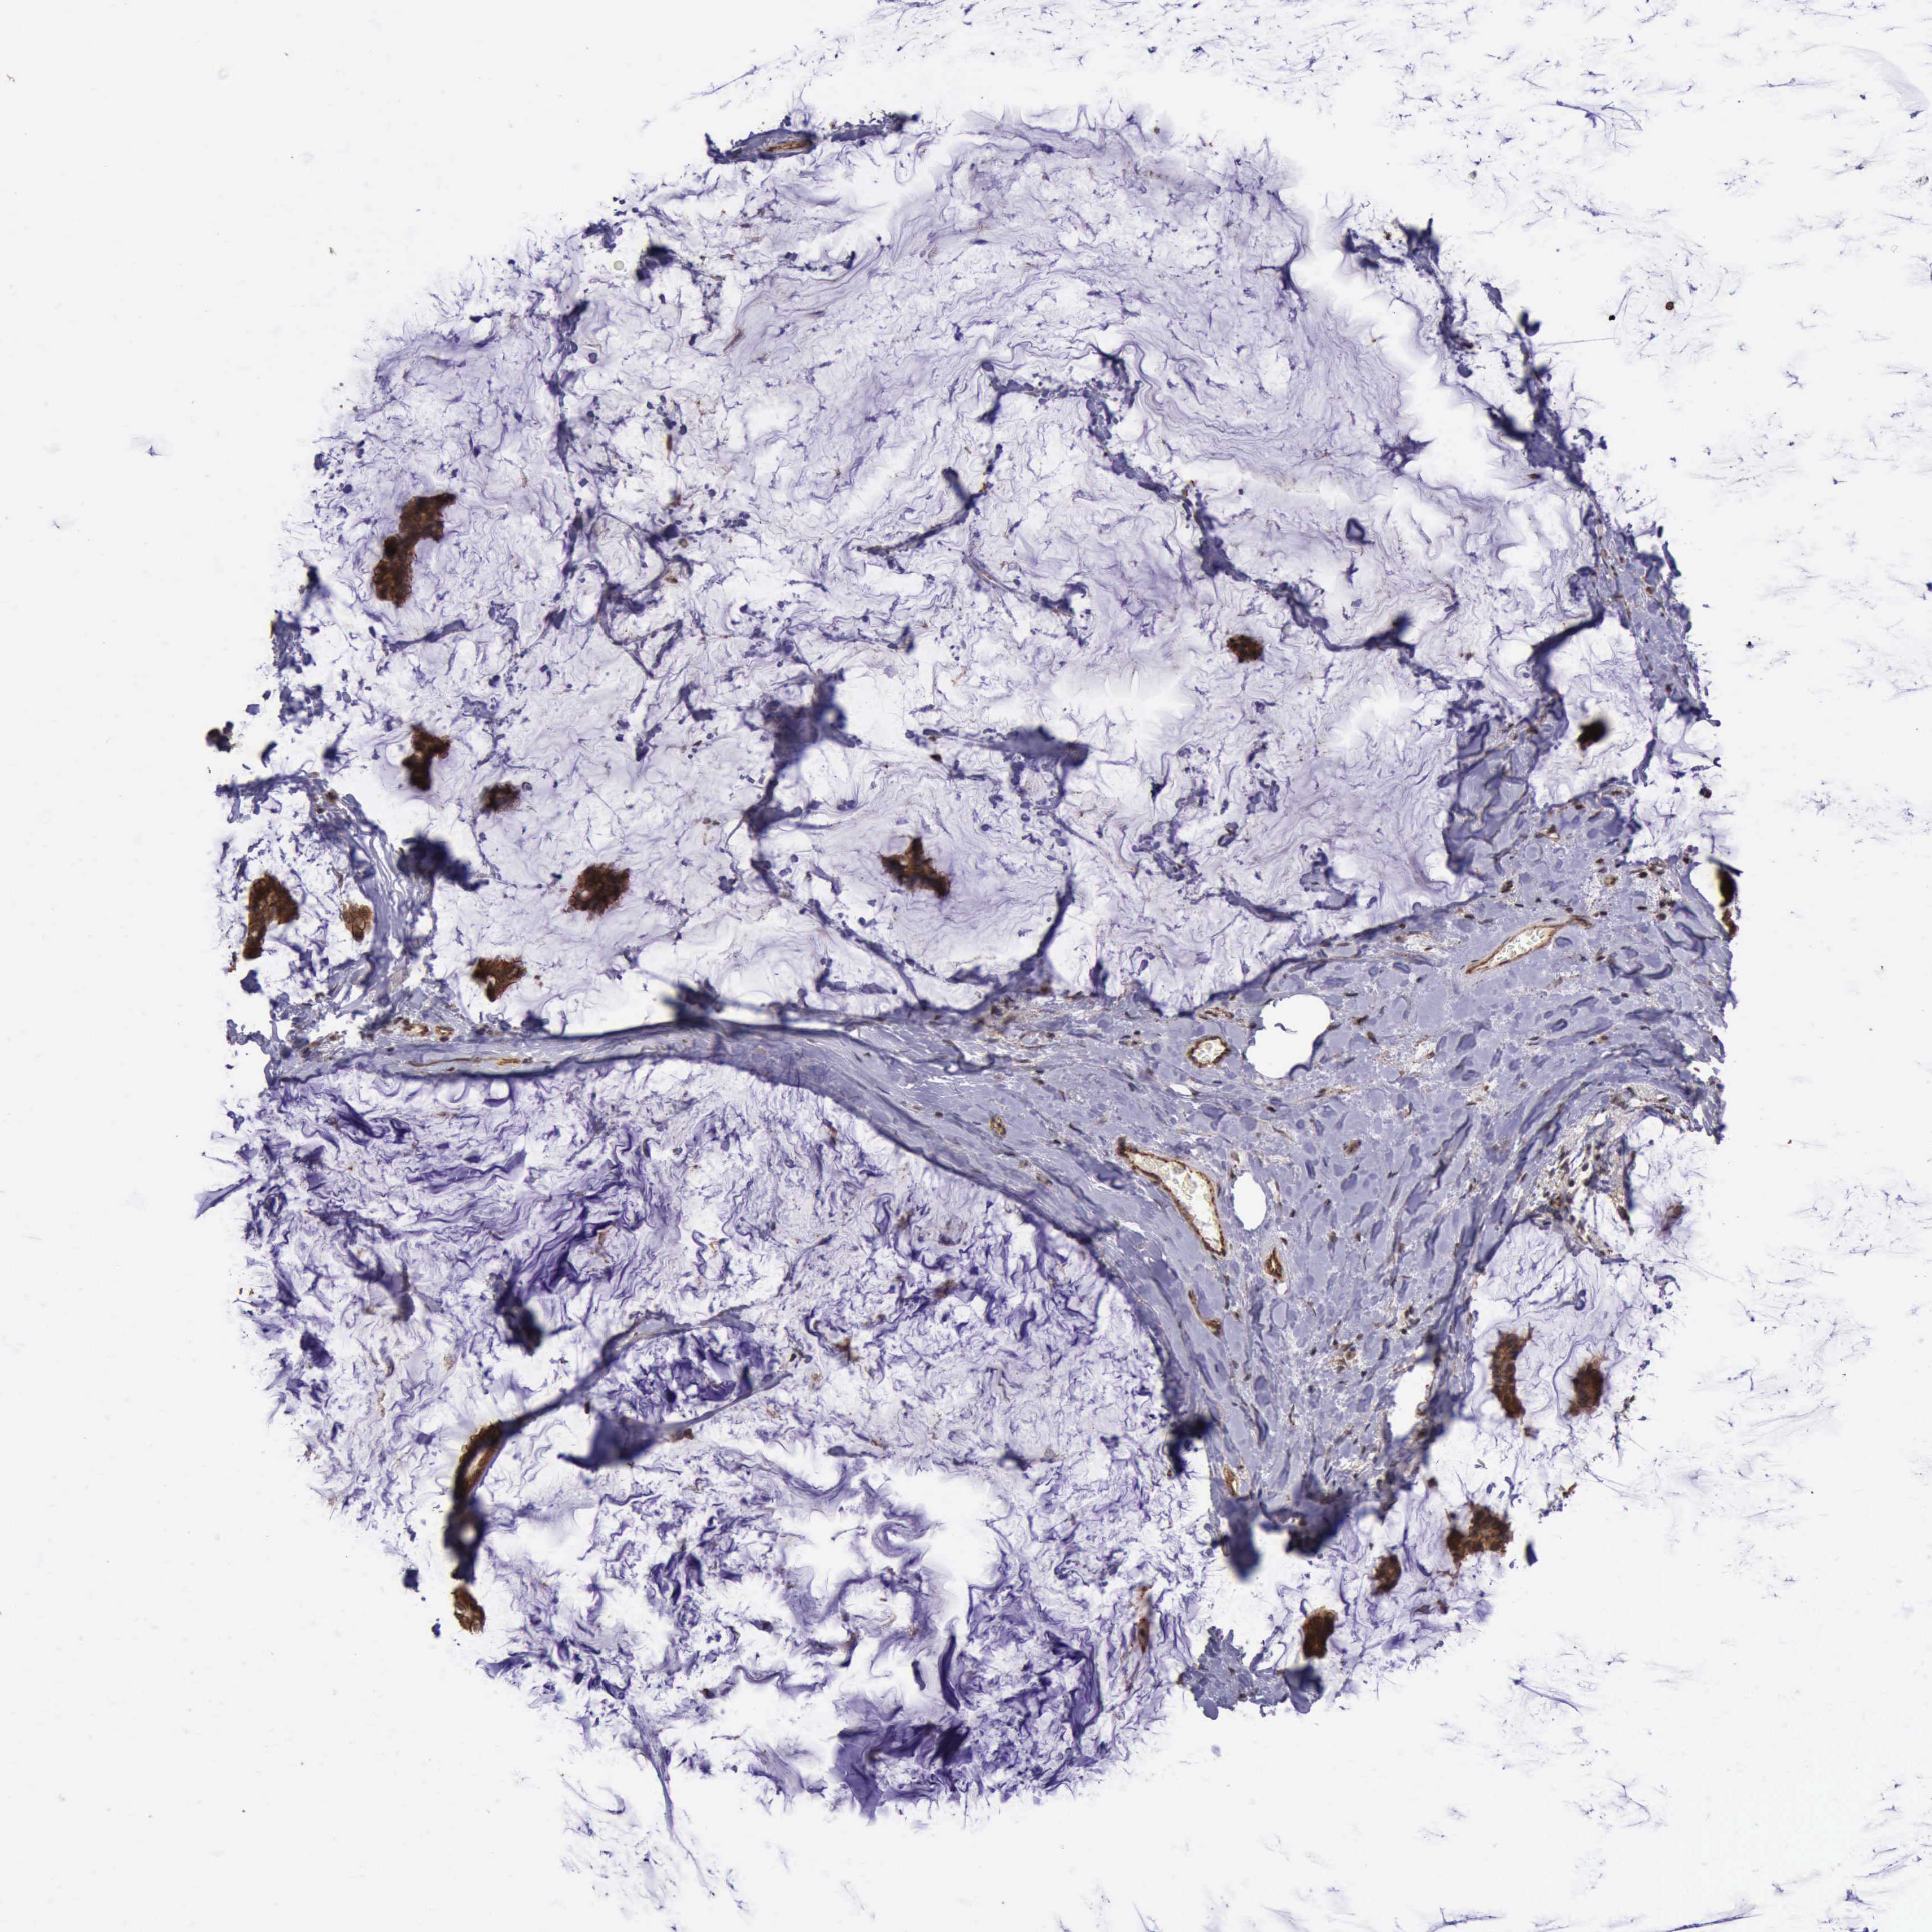

BRCA TCGA BRCA VALIDATION PROTEIN EXPRESSION